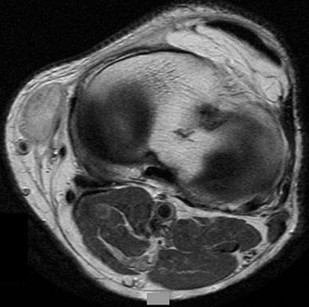

Question 8

A 15-year-old male presents with deep knee pain awakening him at night. Radiographs show a permeative destructive lesion in the distal femoral metaphysis with a 'sunburst' periosteal reaction and Codman's triangle.

Biopsy confirms high-grade conventional osteosarcoma. What is the most critical prognostic factor for long-term overall survival in this patient?

Explanation

For localized high-grade osteosarcoma, the most important prognostic indicator is the histologic response to neoadjuvant chemotherapy. This is evaluated during the definitive resection. A 'good response' is typically defined as greater than 90% or 99% tumor necrosis. Patients who achieve this level of necrosis have a significantly improved disease-free and overall survival rate compared to 'poor responders' who have extensive viable tumor cells remaining.